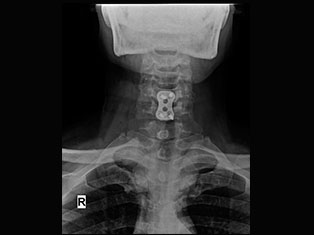

Degenerative Spine

The phrase "degenerative changes" in the spine refers to osteoarthritis of the spine. Osteoarthritis is the most common form of arthritis. Doctors may also refer to it as degenerative arthritis or degenerative joint disease.